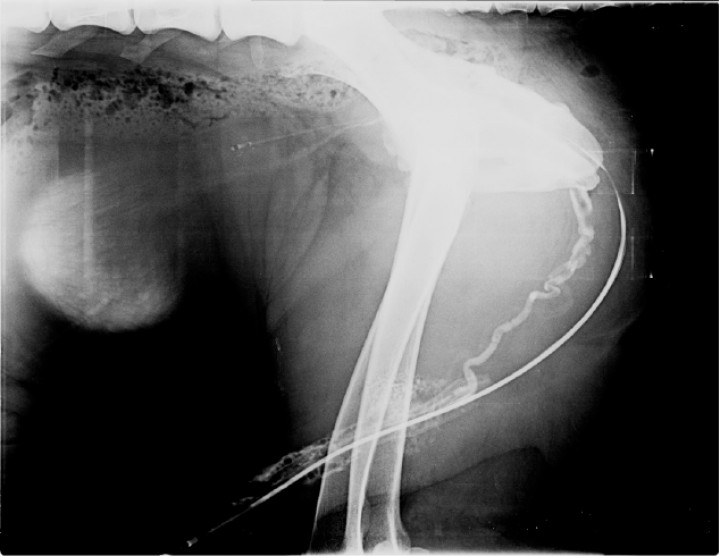

<p>Misma imagen que la Figura 1. Se observa el recorrido de la uretra por la presencia de la sonda uretral y la columna de contraste positivo, con morfología normal en sus segmentos perineal e intrapelviano. Craneal a la uretra perineal se aprecia una segunda estructura tubular, de recorrido sinuoso, que se extiende desde el área intrapelviana hasta el pene. Esta estructura es compatible, por morfología y localización, con la vena dorsal del pene, que desemboca en la vena pudenda interna a nivel de la entrada de la pelvis.</p>

Misma imagen que la Figura 1. Se observa el recorrido de la uretra por la presencia de la sonda uretral y la columna de contraste positivo, con morfología normal en sus segmentos perineal e intrapelviano. Craneal a la uretra perineal se aprecia una segunda estructura tubular, de recorrido sinuoso, que se extiende desde el área intrapelviana hasta el pene. Esta estructura es compatible, por morfología y localización, con la vena dorsal del pene, que desemboca en la vena pudenda interna a nivel de la entrada de la pelvis.